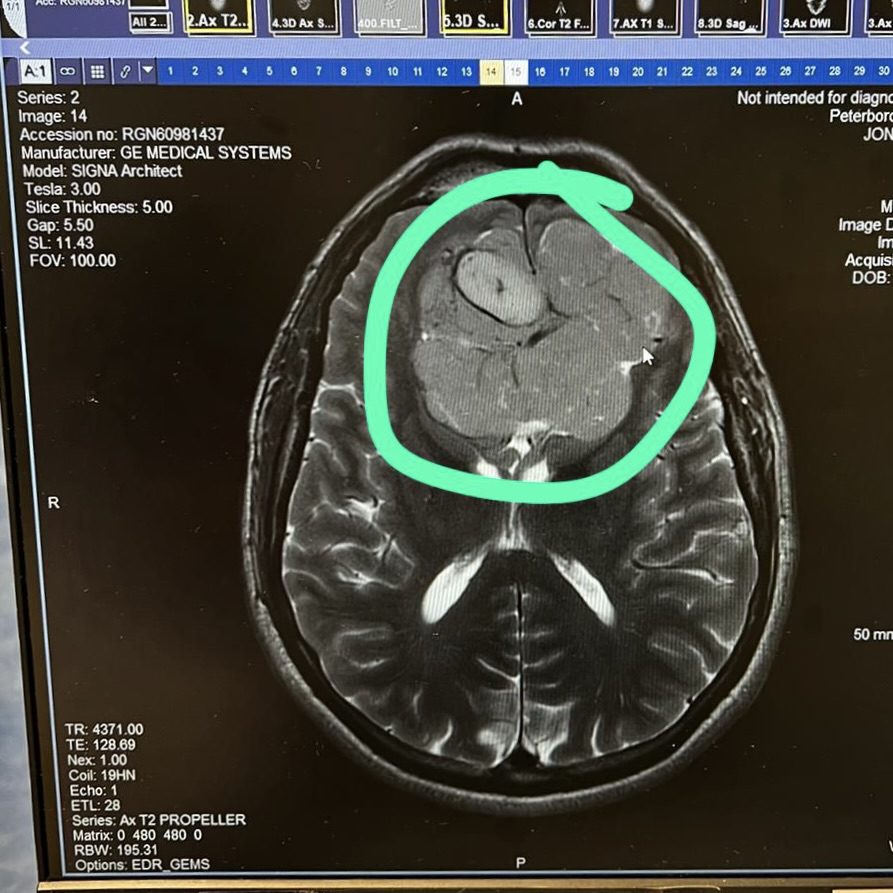

A brain tumour the size of a tennis ball

After this second MRI scan, I met with a specialist who said “It is never easy to hear this kind of news, but you have a tumour in your brain the size of a tennis ball”.

As you can imagine, I had difficulty comprehending what they had just said. A tennis ball-sized tumour in my head? How is that possible?